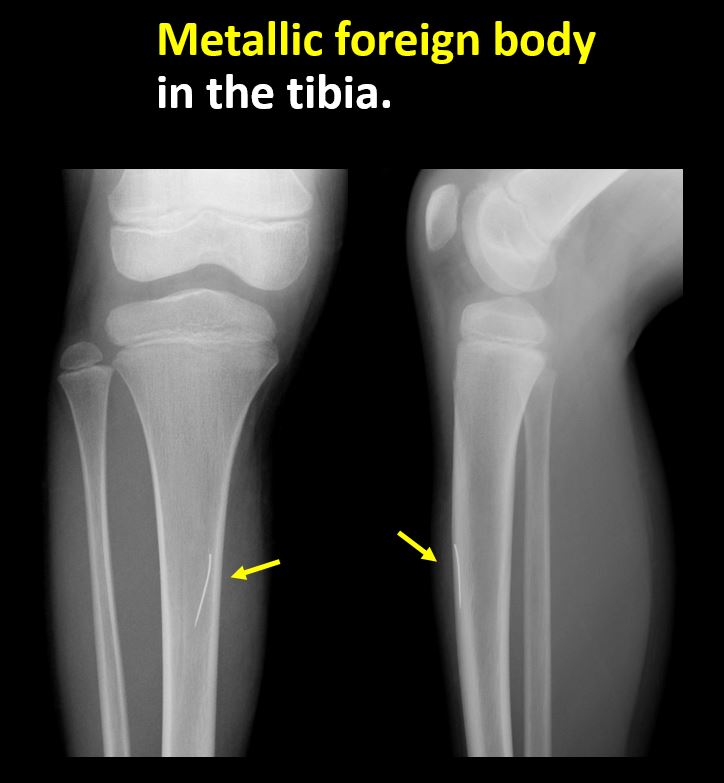

There is a radiodense or lucent foreign body. [Yes/No]